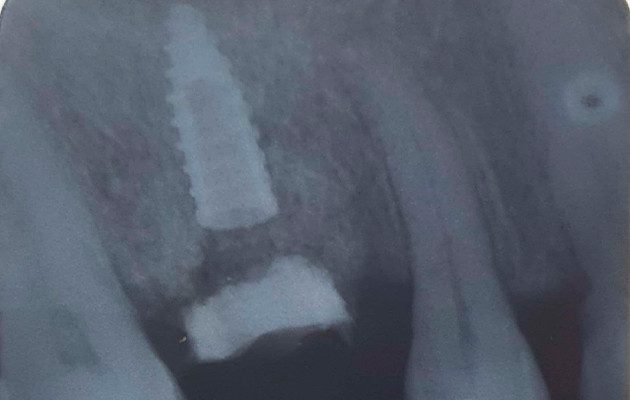

3 | Exame tomográfico da região do dente 16.

13 | Radiografia periapical realizada logo após a instalação do Implante com Cicatrizador personalizado.